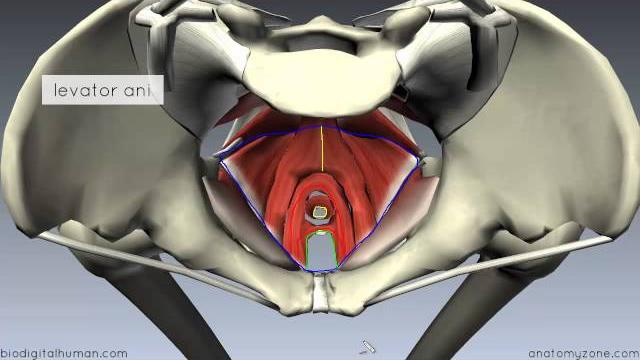

Для вашего запроса найдены видео: Guided meditation for pelvic floor relaxation | femfusion fitness, Best exercises for prolapse and bladder leaks safely strengthen your pelvic floor!, Clinical pelvimetry